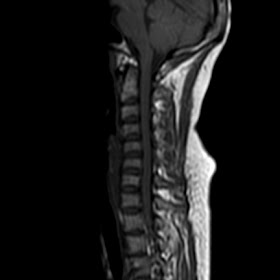

Radiological images: